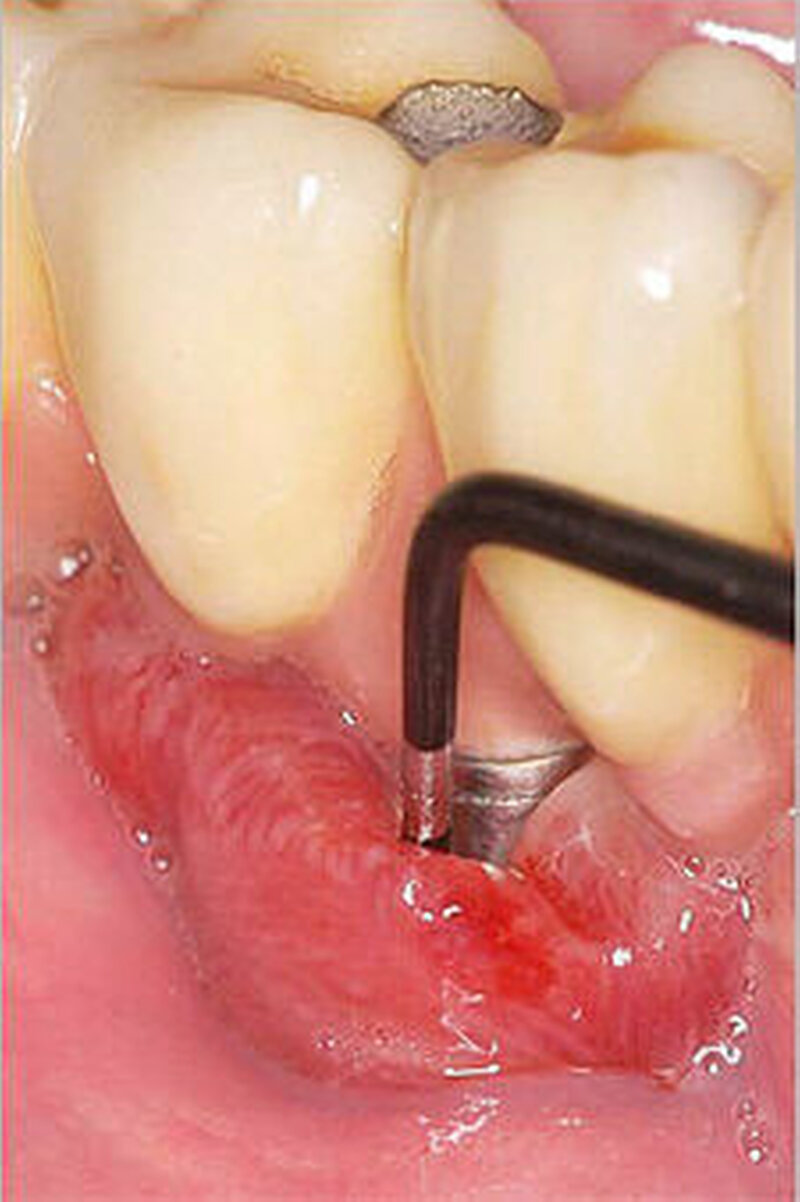

• Diabetes mellitus scheint in den ersten Jahren kein erhöhtes Risiko für periimplantäre Entzündungen darzustellen. Im Gegensatz dazu scheint das Risiko für periimplantäre Entzündung mit steigender Dauer nach der Implantation anzusteigen.

• Aufgrund von Hinweisen auf eine verzögerte Osseointegration sollte die Indikation für eine Sofort- und Frühbelastung kritisch gestellt werden.

• Da Patienten mit Diabetes mellitus ein höheres Risiko für Periimplantitis aufweisen, sollte eine risikoadaptierte Nachsorge nach Implantatinsertion erfolgen.

• Bei Anwendung augmentativer Verfahren sollte ein zweizeitiges Vorgehen unter Berücksichtigung von Art und Umfang der chirurgischen Maßnahmen bevorzugt werden.